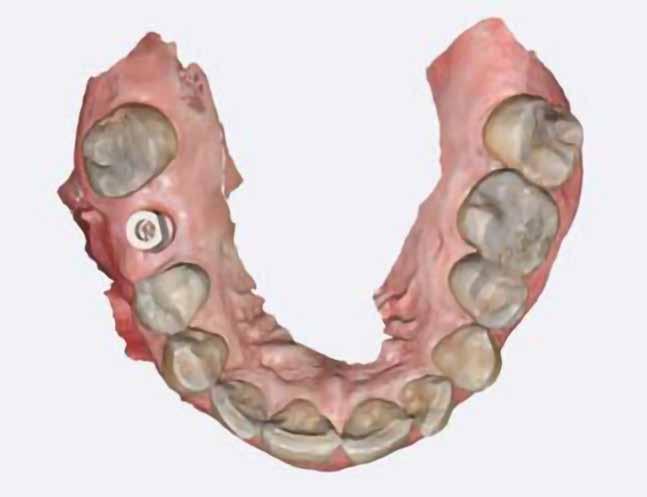

Digitális intraorális scan

Egy héttel a második műtét után intraorális szkennelést végeztünk Medit i500 scannerrel (Medit), a gyártó szkennelési protokollját követve (7. ábra). A gyógyulási csavarok eltávolítása után CERALOG scanbodykat (PEEK-titánötvözet csavar) helyeztünk el az implantátumokba. A fogszín meghatározását digitálisan, a Rayplicker (Borea) segítségével végeztük. A protetikai pótlás tervezéséhez poliphenilszulfon felépítményeket alkalmaztunk. Minden koronát digitálisan rendeltünk ugyanabból a fogászati laboratóriumból, és kerámiakoronákat választottunk minden esetben.

7. a–d ábra: Digitális intraorális szkennelések az implantátum felszabadítása után. 1. eset (a). 2. eset (b). 3. eset (c), 4. eset (d).